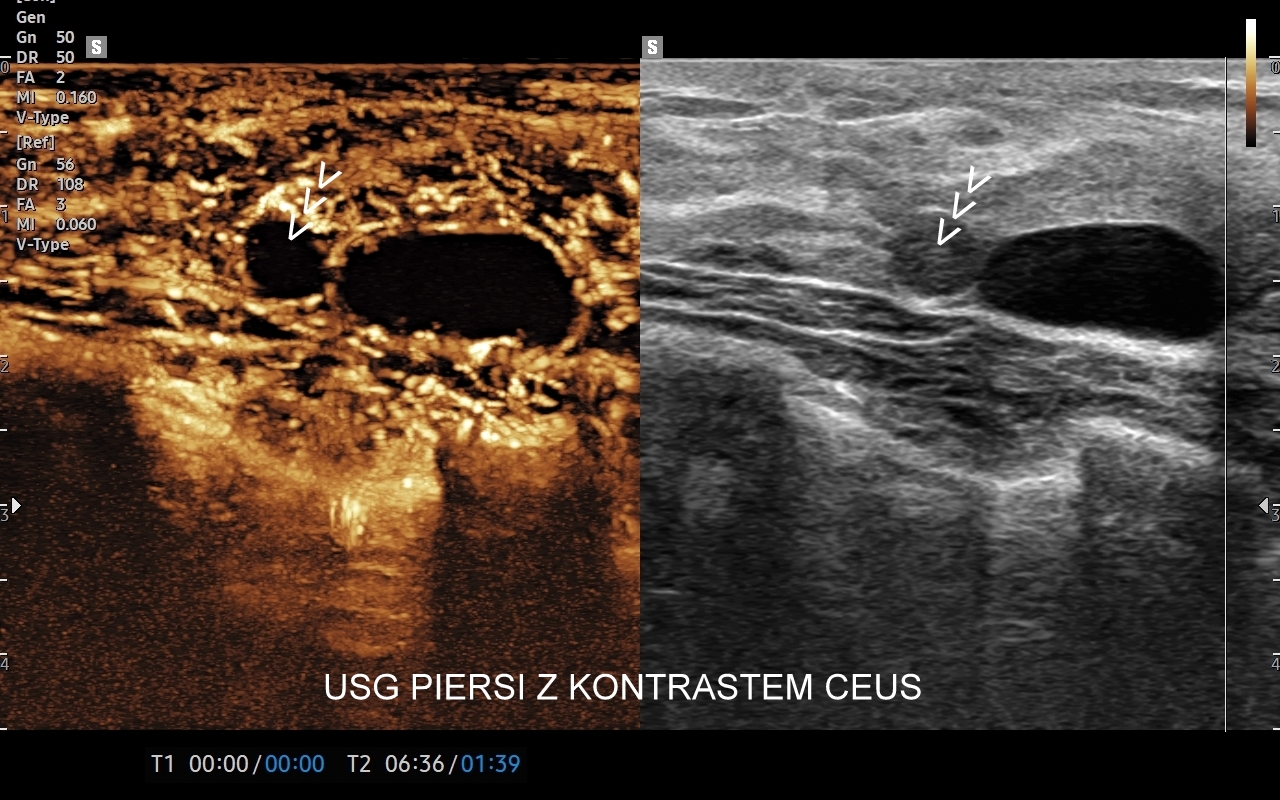

USG piersi z kontrastem CEUS

Badanie USG piersi z kontrastem (CEUS) jest najnowszą metodą diagnostyczną piersi i rozwinięciem badania multiparametrycznego USG (MPUS). Główną rolą badania CEUS piersi jest zwiększenie precyzji oceny guzków piersi pod kątem kwalifikacji w skali BIRADS, a przez to uniknięcie niepotrzebnych biopsji piersi. W przeciwieństwie do innych metod diagnostycznych zasadniczą zaletą badania CEUS jest możliwość jednoznacznego wykazania lub wykluczenia unaczynienia guzka piersi. Podejrzany guzek, którego unaczynienia lub cech nie można jednoznacznie ocenić w standardowym badaniu USG można poddać badaniu USG z kontrastem. Otóż w przypadku, gdy zmiana nie posiada unaczynienia to nie jest ona nowotworem. Niezależnie od kwalifikacji guzków łagodnych badanie CEUS ma możliwość w wielu wypadkach uwidocznienia ukrytych dodatkowych cech świadczących o złośliwości guzka.

Badanie CEUS jest bezpieczne dla organizmu i nie obciąża nerek, w przeciwieństwie do kontrastu przy tomografii komputerowej czy rezonansie magnetycznym. Pierwszym lekarzem w Polsce, który ambulatoryjnie zastosował metodę CEUS piersi jest dr Tomasz Szczepański; badanie odbyło się w 2024 r. we Wrocławiu w Opiece Medycznej Golden Care.